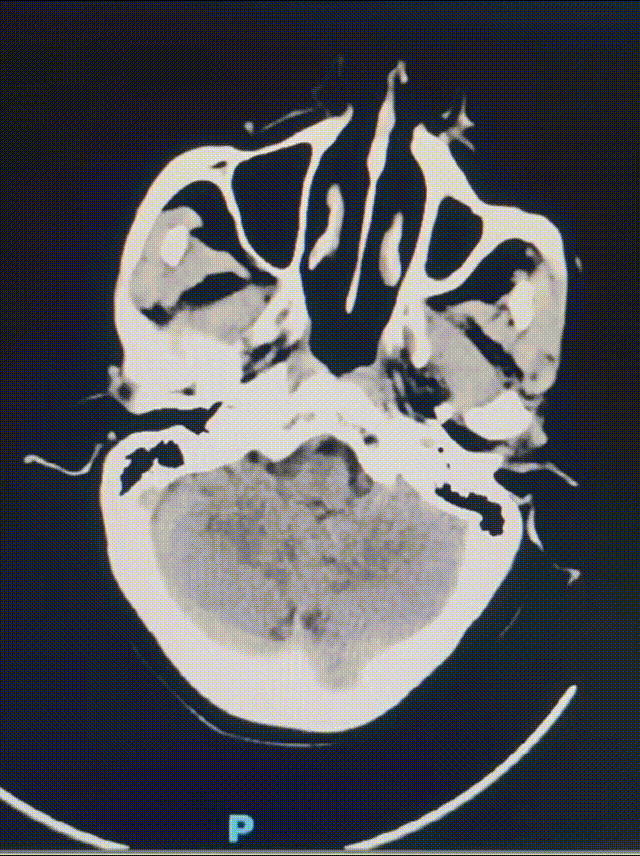

术前影像

房颤栓塞致左侧大脑中动脉闭塞。

动脉长鞘怎么置入健谈•一鞘双能|温昌明教授团队:BMAX088球囊长鞘治疗左侧大脑中动脉闭塞一例_https://www.jmylbn.com_新闻资讯_第3张

无急性大面积脑梗死早期表现